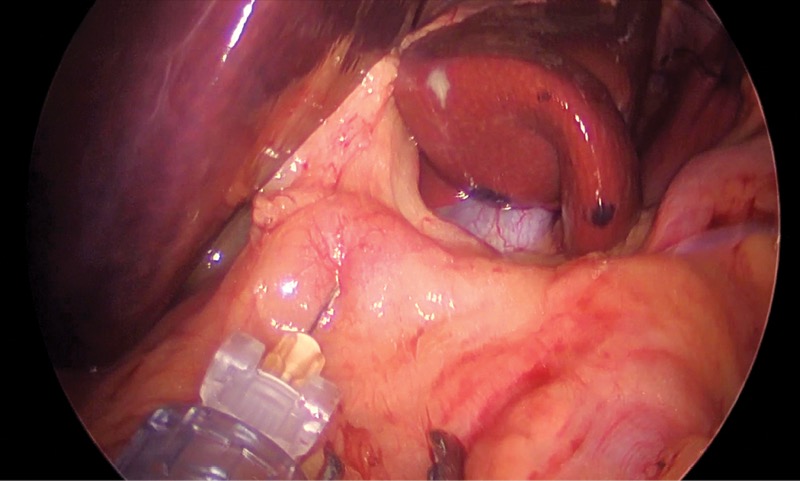

“Of course, there were issues when we first started performing the technique,” Dr. Sharma said in an interview with General Surgery News. “How do you expose the ganglia? What combination of drugs to inject? What’s the best way to inject the mixture? But now that I’ve mastered it, it takes only a few minutes to perform, and without the use of CT scan, fluoroscopy or x-ray, which are used in traditional approaches to the celiac ganglia.

Dr. Sharma performs the block under general anesthesia. After standard port placement in the patient’s abdominal cavity, he incises the peritoneum close to the celiac trunk, where he exposes and identifies three to four ganglia. Using a dedicated probe, he injects 5 to 10 ml of the solution, depending on the size and number of ganglia.

“But if a surgeon can perform foregut surgery, they can certainly expose and numb the ganglia … if shown how to do it properly.” This process will likely be facilitated in the future by a dedicated injection probe Dr. Sharma is currently developing.